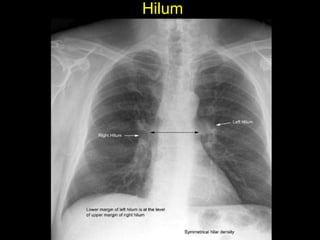

The document discusses the anatomy of the chest x-ray and CT scan by describing the lobes of the lungs and their locations. It also mentions the heart, mediastinum, hilum, and ribs. Several axial, coronal, and sagittal CT images are included with labels pointing out structures like the trachea, bronchi, lobes of the lungs, and fissures. In summary, the document provides an overview of lung and chest anatomy as seen on x-rays and CT scans through text descriptions and labeled medical images.